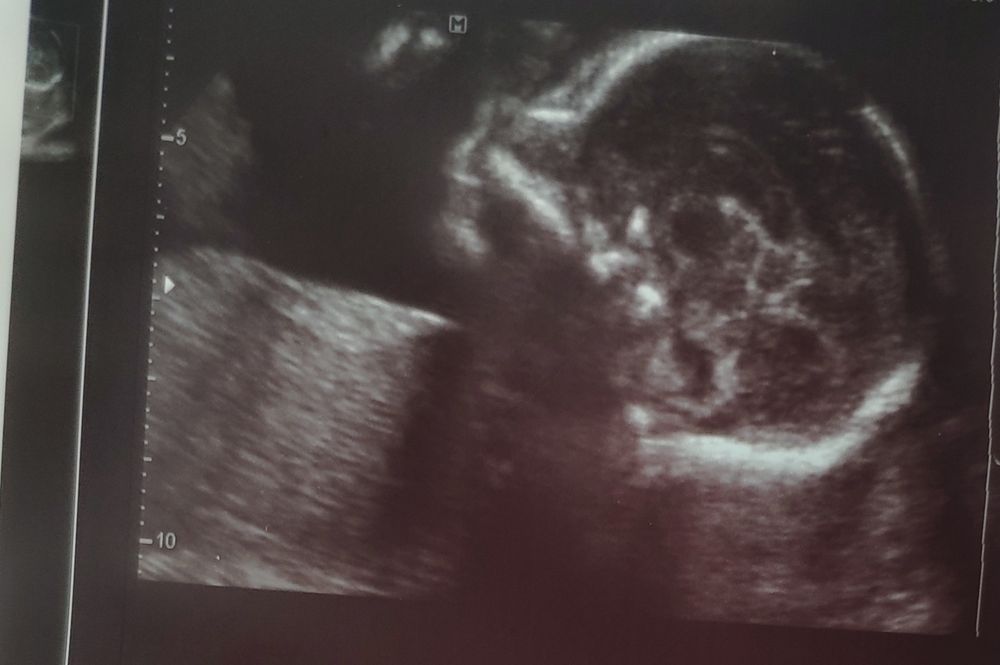

Второй скрининг

Кто бы там не был, определенно очень красивый малышочек там сидит 🥰😻🤗

Мои поздравления🎉🎊 самое главное, что все хорошо👍 я тоже вижу тут мальчика. Как говорила моя узистаа, что мальчики на таких сроках более лобастые. Напишите пожалуйста потом как узнаете пол)) я бы не выдержала и уже взорвала конверт 😆

Поздравляю вас с хорошим скринингом. Мне почему-то на фотке тоже мальчик представляется.

Mi Mi, мы узнаем кто у нас на следующих выходных.....мне все-равно кто будет,но хочется платьев и бантов 😂А смотрю на фото и понимаю,что это сыночек))))Хотя посмотрела фото УЗИ в интернете,не всегда похожи)))